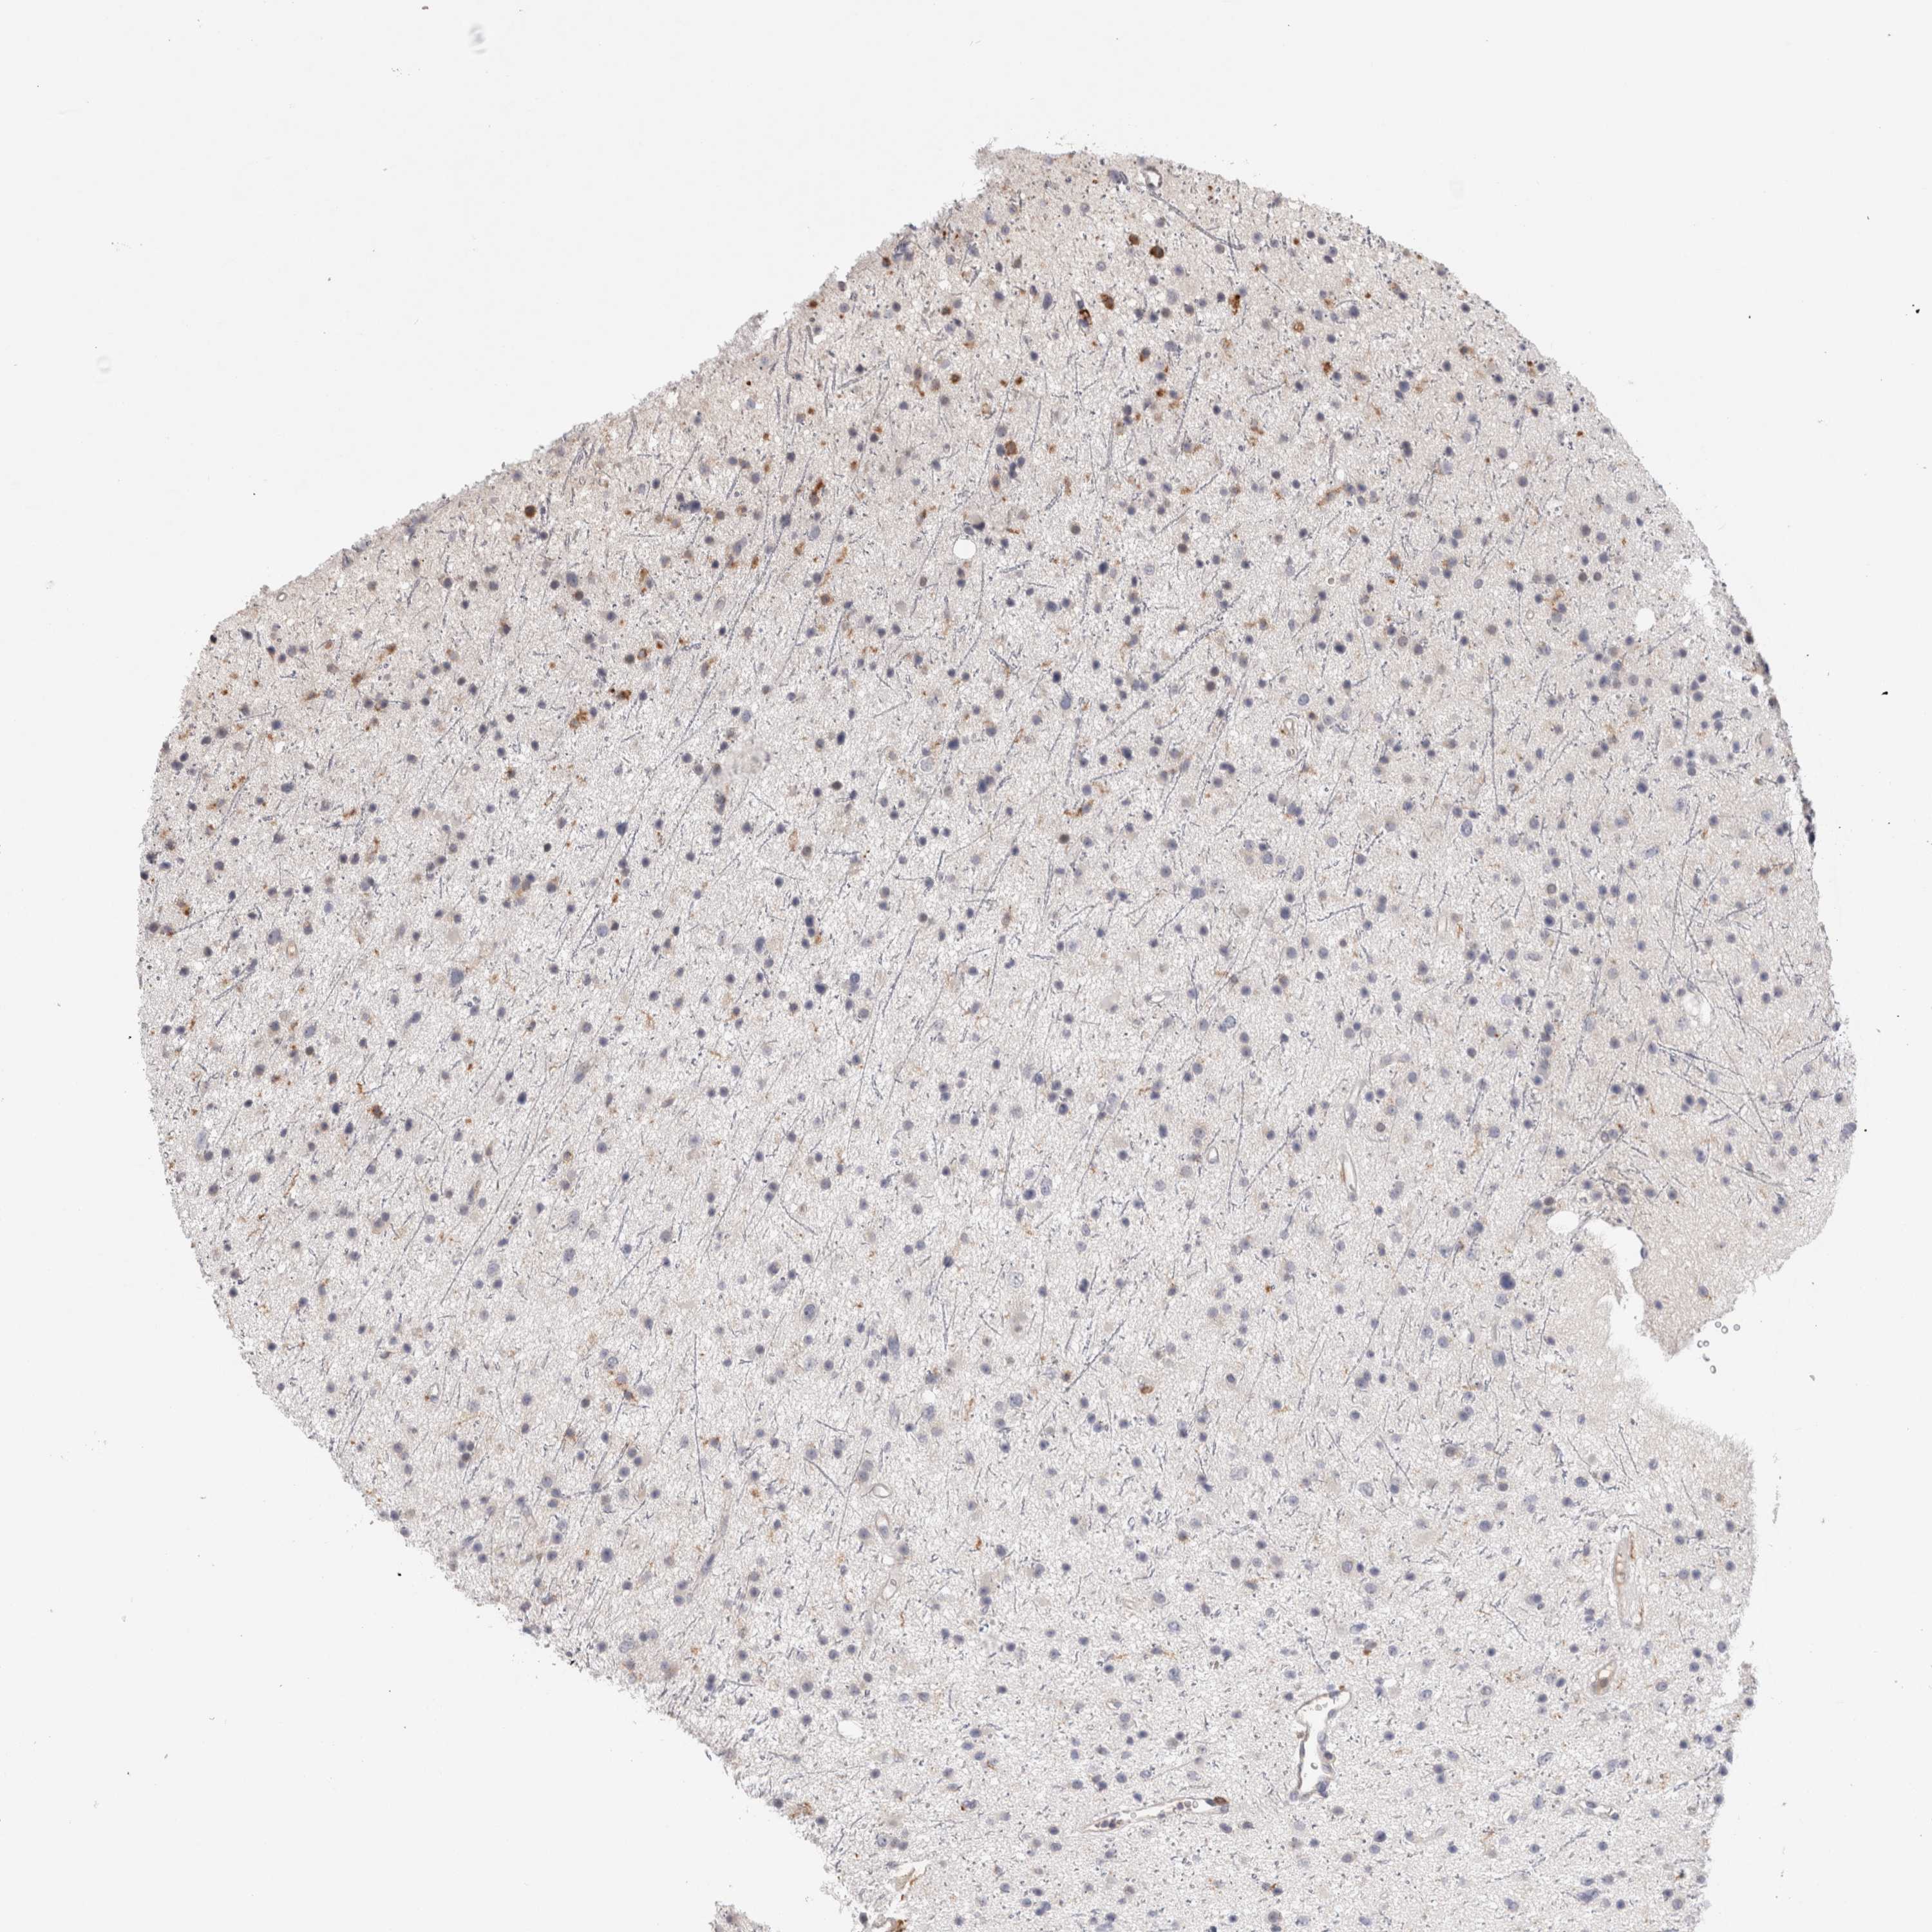

GLIOMA - Protein expressioni

A mouse-over function shows sample information and annotation data. Click on an image to view it in a full screen mode. Samples can be filtered based on level of antibody staining by selecting one or several of the following categories: high, medium, low and not detected. The assay and annotation is described here.

Note that samples used for immunohistochemistry by the Human Protein Atlas do not correspond to samples in the TCGA dataset.

Antibody stainingi

Antibody staining in the annotated cell types in the current human tissue is reported as not detected, low, medium, or high, based on conventional immunohistochemistry profiling in selected tissues. This score is based on the combination of the staining intensity and fraction of stained cells.

Each image is clickable and will lead to virtual microscopy that enables deeper exploration of all samples and also displays staining intensity scores, fraction scores and subcellular localization as well as patient and tissue information for each sample.

Antibody HPA003903

Antibody HPA072756

Antibody CAB026000

Staining

High

Medium

Low

Not detected

Intensity

Strong

Moderate

Weak

Negative

Quantity

>75%

75%-25%

<25%

None

Location

Nuclear

Cytoplasmic/membranous

Cytoplasmic/membranous,nuclear

Glioma, malignant, High grade

Glioma, malignant, NOS

Glioma, malignant, Low grade